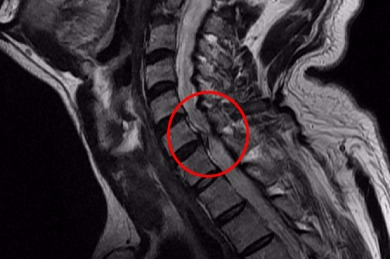

목디스크란 목뼈 사이에 있는 디스크가 손상되어 신경을 압박하는 질환을 의미합니다. 디스크는 젤리와 같은 수핵과 섬유륜으로 구성되어 있습니다. 섬유륜이 손상되면 수핵이 밖으로 밀려나와 신경을 압박하게 됩니다.

목디스크는 주로 잘못된 자세, 과도한 스트레스, 외상 등으로 발생합니다. 잘못된 자세로 장시간 컴퓨터를 사용하거나 운전을 하면 목에 무리가 가고 디스크가 손상될 수 있습니다.

또한 과도한 스트레스는 근육을 긴장시켜 디스크에 손상을 줄 수 있습니다. 외상은 교통사고, 운동 중 충격 등으로 목뼈가 부러지거나 골절되면 디스크가 손상될 수 있습니다.